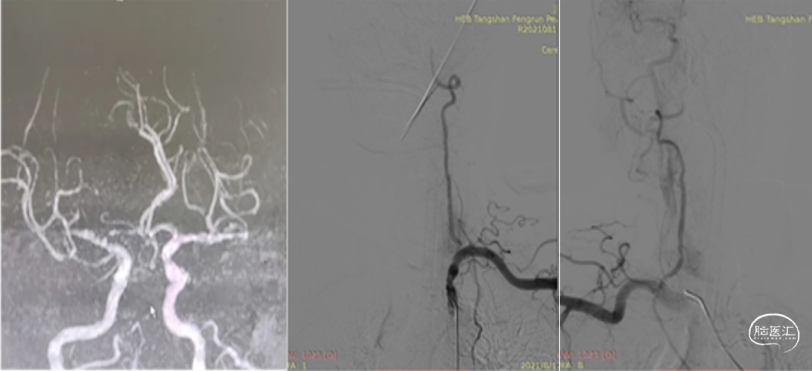

三、 经桡动脉入路大脑中动脉急性闭塞取栓

大脑中动脉急性闭塞常规经股动脉入路建立血管通路急性取栓,但老年高龄患者常常血管迂曲、Ⅲ型主动脉弓、髂动脉狭窄或闭塞,通路建立存在困难,可选择经桡动脉入路建立通路,快速实现血管再通,血运重建。经桡动脉入路血管内进入 具有创伤小,术后无须卧床,血管穿刺部位并发症少,便于术后护理的优势。

经桡动脉入路赛诺远端通路导管大脑中动脉取栓

病例简介:

患者,jgh,女性,75岁。主诉:“突发言语不利,左侧肢体无力2小时"入院。

现病史:患者于2小时前突发言语含糊,吐字不清,头晕、头昏,左侧上下肢无力。患者之女自驾车送来我院就诊。既往史:有高血压病史5年余,2年前患右侧基底节区脑梗死经治疗好转,无明显后遗症。专科查体: 意识清,言语含糊,左侧上下肢肌力3级。左侧巴宾斯基(++),NiHSS评分7分。辅助检查:核磁DWI显示:右侧基底节区多发点状梗塞灶,考虑低灌注。MRA显示:右侧大脑中动脉M1段以远端未显影,考虑ICAS病变。

术前诊断:

1、急性大脑中动脉闭塞性脑梗死(大血管闭塞型)2、高血压2级(高危组)

病情讨论:

患者老年女性,既往有高血压、脑梗死闭塞,本次急性发病,核磁共振检查:DWI显示多发点状梗死灶,考虑为低灌注。

距离发病2小时,NiHSS评分7分,符合大血管病变,在溶栓和血管内治疗6小时时间窗内,结合病史和检查,考虑ICAS病变。静脉溶栓不能达到血管再通。

给予替罗非班负荷量推注后行血管内介入治疗。经和家属沟通,同意行血管内介入治疗。

手术方案:

1、患者老年女性,可能存在Ⅲ型主动脉弓,介入通路建立存在困难。

2、老年女性,经股动脉入路术后平卧困难。

3、经查体右侧桡动脉搏动明显,血管较粗。拟行桡动脉穿刺入路行右侧大脑中动脉闭塞血管再通。

手术策略:

1、置入7F薄壁桡动脉鞘。

2、260cm 035in亲水泥鳅导丝携带4F 140cm西蒙导管外衬7F-105cm赛诺远端通路导管超选右侧颈总动脉建立血管介入通路。

3、沿赛诺远端通路导管输送5F-125cm中天天巡中间导管到达右侧颈内动脉C3段;微导丝携带微导管辅助5F天巡中间导管大脑中动脉M1段。

4、微导丝携带微导管机械碎栓;必要时进行球囊扩张血管成形、支架植入。